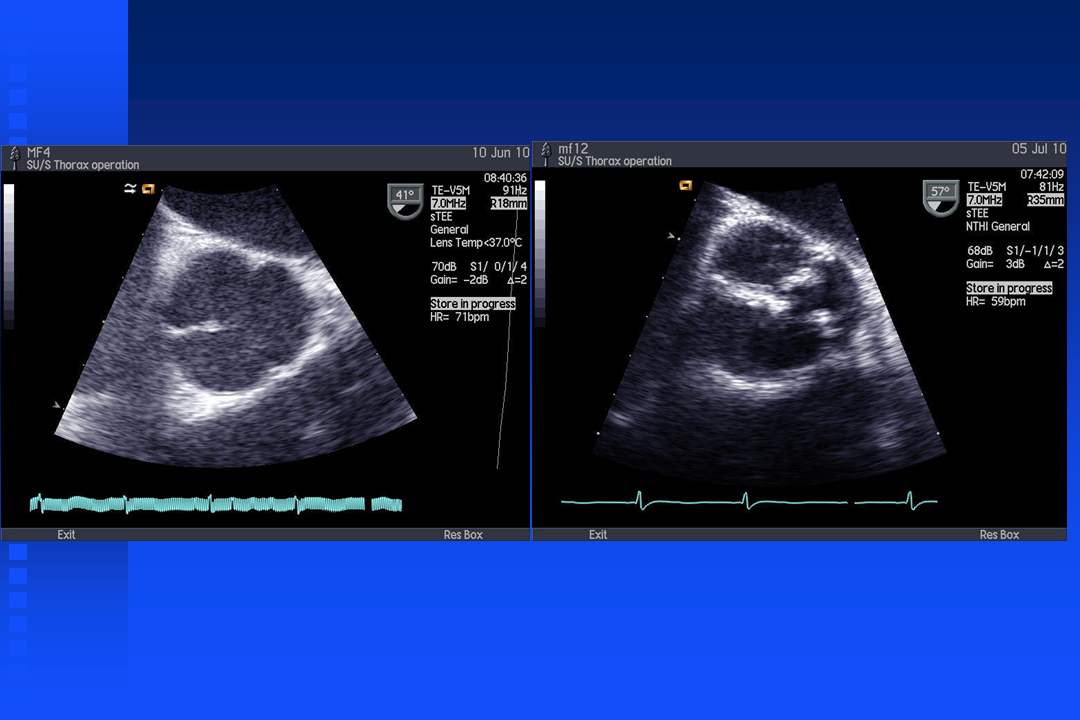

Short film Bicuspid Valve

Short film aortic valve with regurgitation

Short film mitral relaps

Short film mitral relaps with color doppler

Mitral Valve relaps